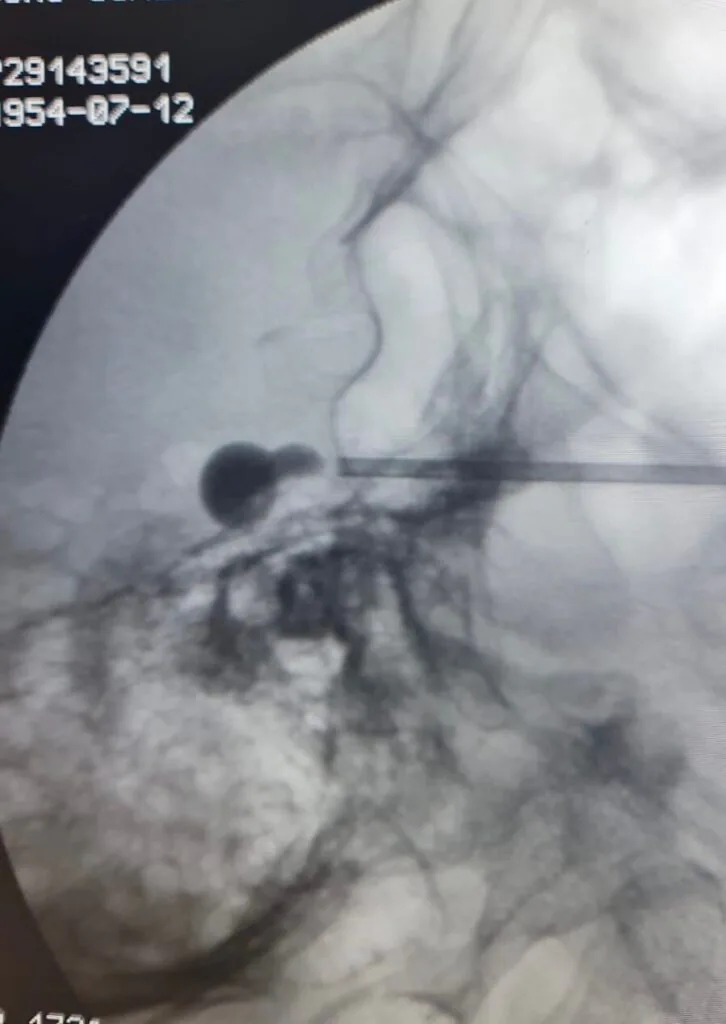

- Compressão do gânglio por balão: consiste no posicionamento de um balão introduzido por uma agulha sob anestesia na saída do trigêmeo para a face, comprimindo o gânglio para resultar em amortecimento do rosto.